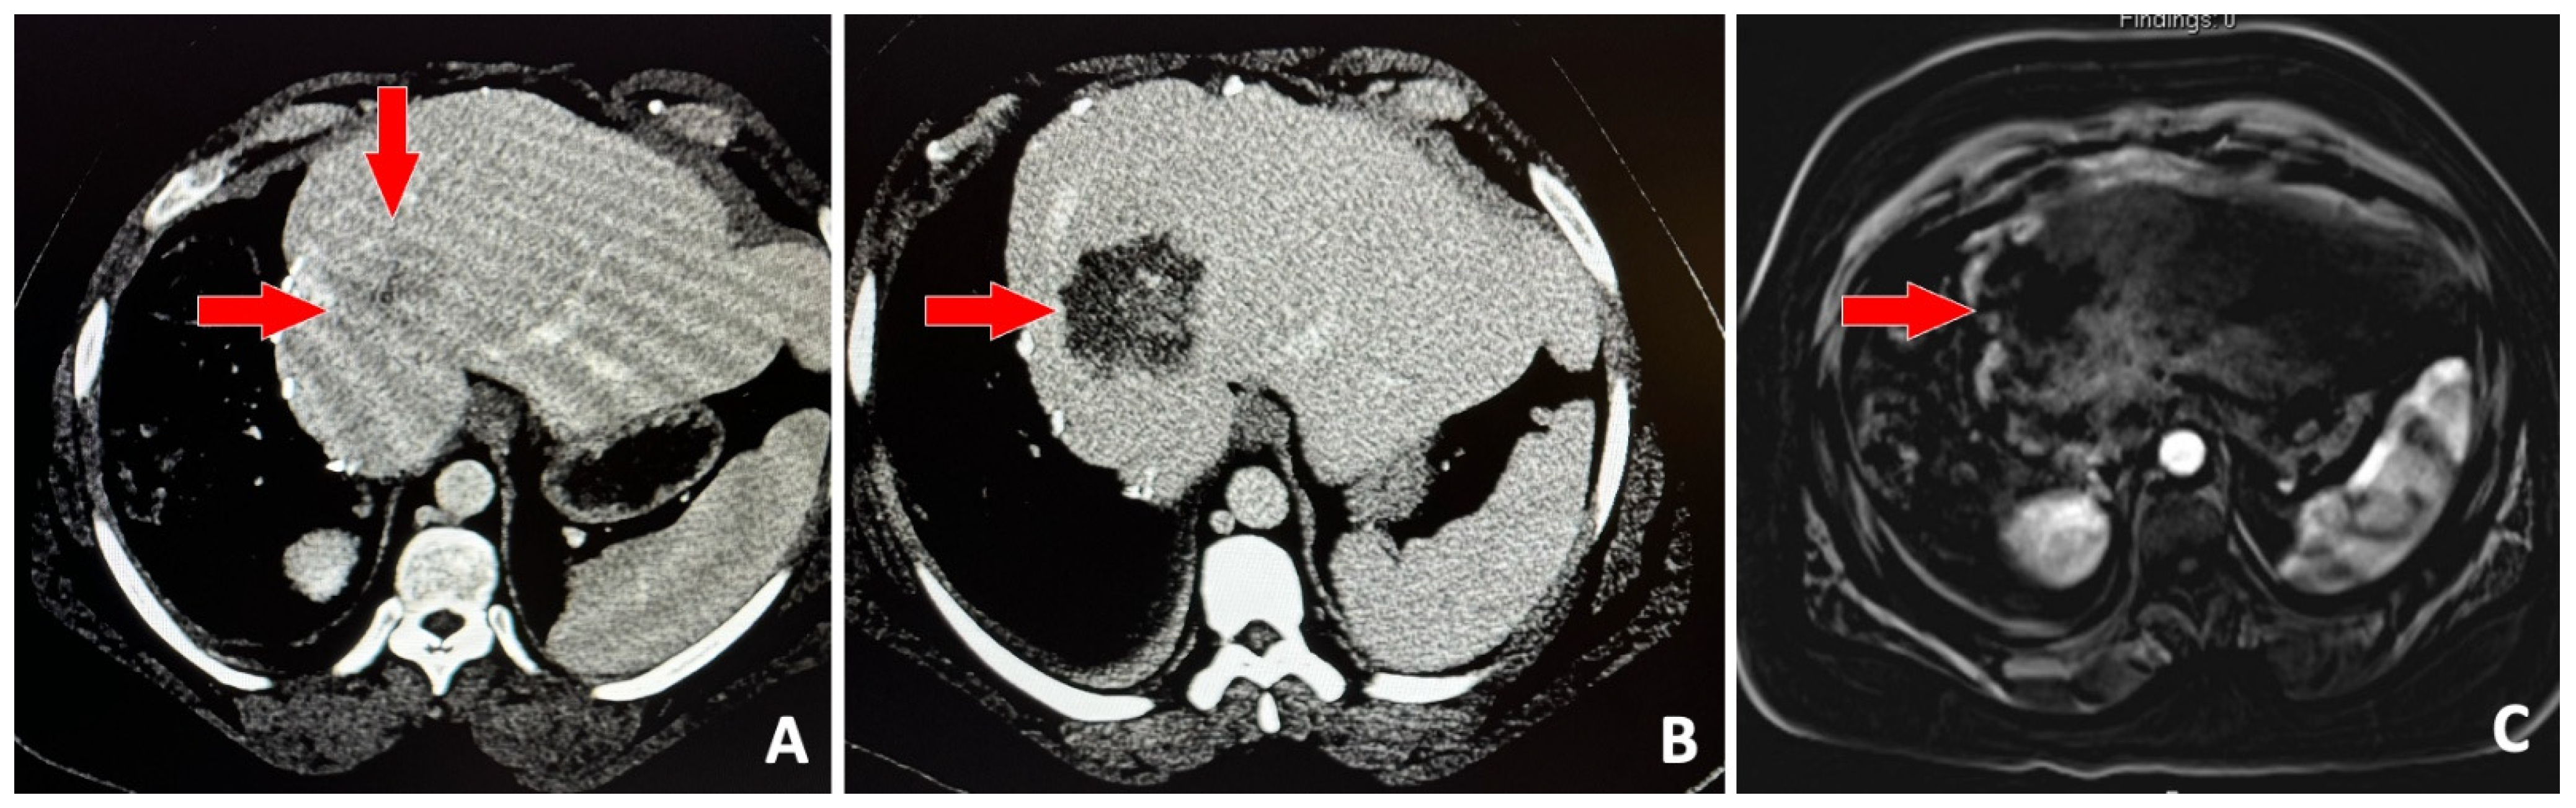

- Vidal-Jove, J.; Serres, X.; Vlaisavljevich, E.; Cannata, J.; Duryea, A.; Miller, R.; Merino, X.; Velat, M.; Kam, Y.; Bolduan, R.; et al. First-in-man histotripsy of hepatic tumors: The THERESA trial, a feasibility study. Int. J. Hyperth. 2022, 39, 1115–1123. [Google Scholar] [CrossRef]

- Wah, T.M.; Pech, M.; Thormann, M.; Serres, X.; Littler, P.; Stenberg, B.; Lenton, J.; Smith, J.; Wiggermann, P.; Planert, M.; et al. A Multi-centre, Single Arm, Non-randomized, Prospective European Trial to Evaluate the Safety and Efficacy of the HistoSonics System in the Treatment of Primary and Metastatic Liver Cancers (#HOPE4LIVER). Cardiovasc. Interv. Radiol. 2023, 46, 259–267. [Google Scholar] [CrossRef]

- Mendiratta-Lala, M.; Wiggermann, P.; Pech, M.; Serres-Créixams, X.; White, S.B.; Davis, C.; Ahmed, O.; Parikh, N.D.; Planert, M.; Thormann, M.; et al. The #HOPE4LIVER Single-Arm Pivotal Trial for Histotripsy of Primary and Metastatic Liver Tumors. Radiology 2024, 312, e233051. [Google Scholar] [CrossRef]

- Vidal-Jove, J.; Serres-Creixams, X.; Ziemlewicz, T.J.; Cannata, J.M. Liver Histotripsy Mediated Abscopal Effect-Case Report. IEEE Trans. Ultrason. Ferroelectr. Freq. Control. 2021, 68, 3001–3005. [Google Scholar] [CrossRef] [PubMed]